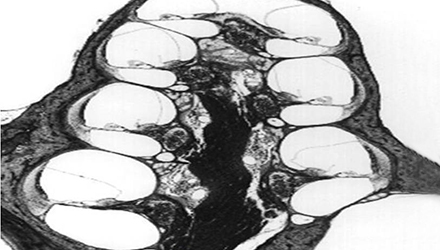

3、膜迷路破滅

膜迷路積水致膜迷路脹破,內(nèi)外淋巴液混合,刺激神經(jīng)感覺細胞導致眩暈、耳鳴、耳聾,裂口愈合則病變暫時恢復。下圖左為前庭膜膨大,右圖為前庭膜破裂,內(nèi)外淋巴交混。